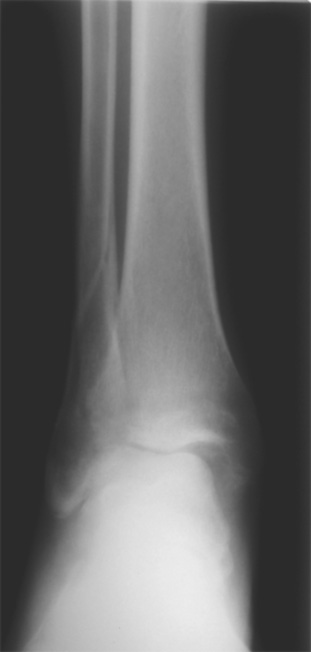

Согласен, на предоставленных рентгенограммах все основания для проведения открытого остеосинтеза.

Здесь представлено решение похожей проблемы. Больной в течение года лечился консервативными мерами, и боли в голеностопе были основным показанием к операции.

Проведена обычная стандартная процедура по исправлению неудовлетворительного состояния голеностопного сустава, где кроме удлинения малоберцовой с применением compression tension device за проксимальный конец пластины, проведено замещение трикортикальным графтом из крыла, освобождение синдесмоза и медиальной щели от

фибротических масс с фиксацией.